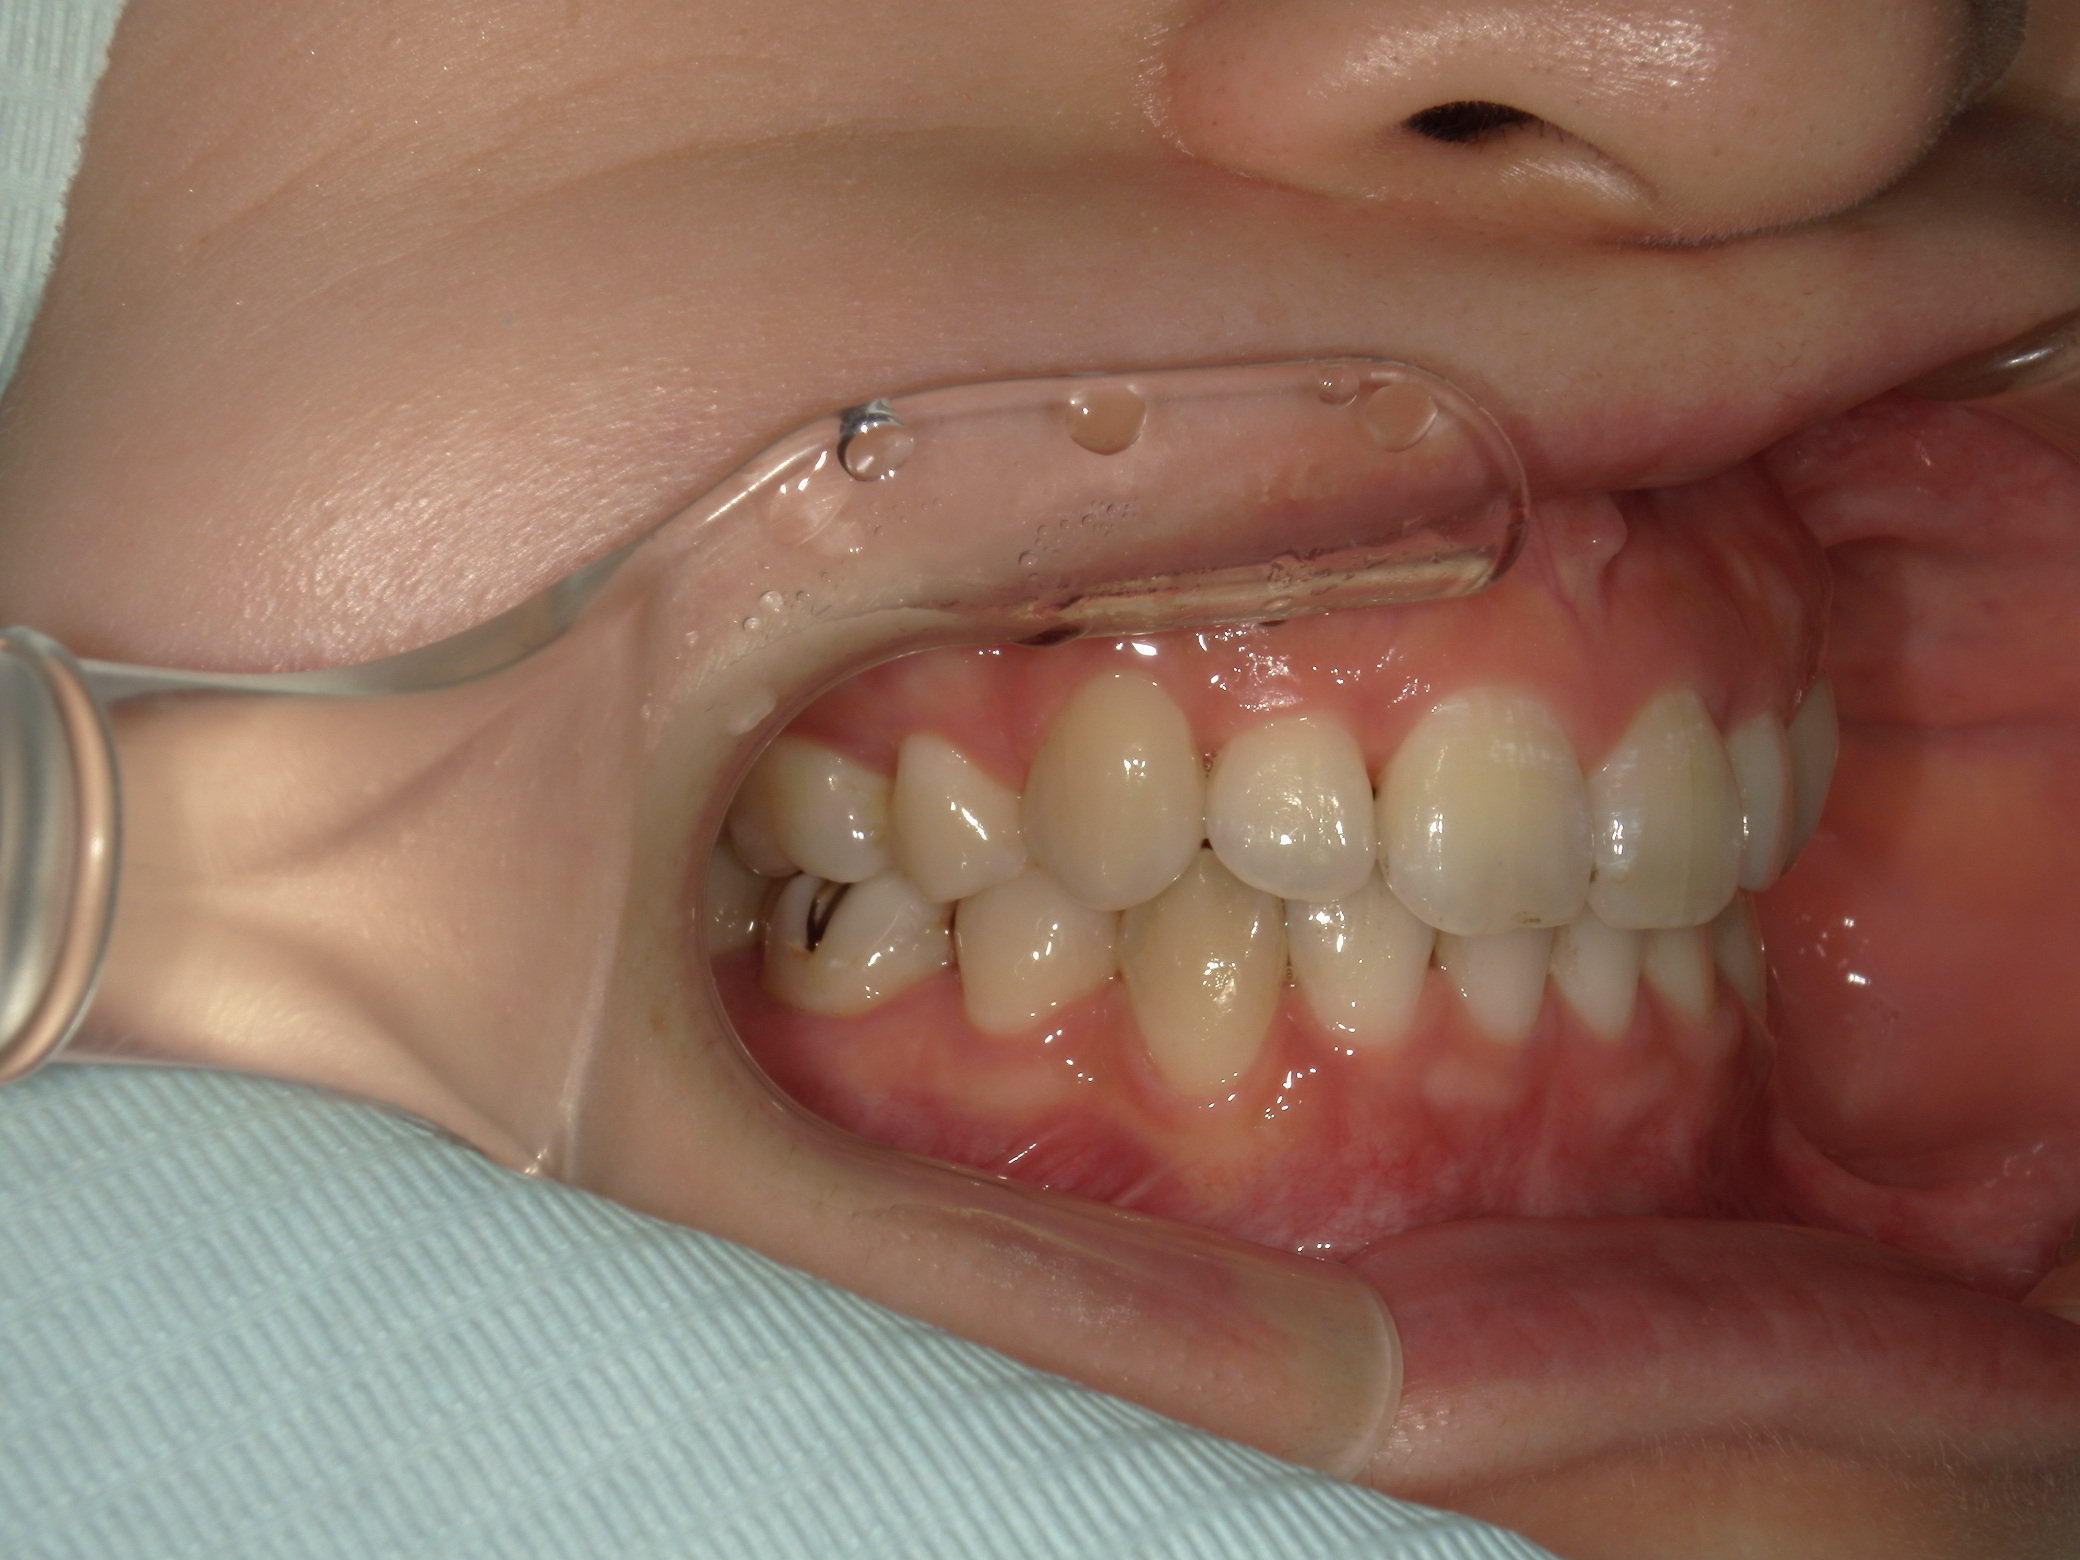

上下顎に叢生(歯並びのガタガタ) と部分的な反対咬合を認める。

前歯の反対咬合は顎位の変化を示す兆候であるため、矯正治療と並行して顎関節症に対するケアが必要。

本症例は上下小臼歯抜歯により叢生解消のスペースを獲得し、下顎位の後退があることからダイレクトスプリント治療を併用して顎位の安定を求めた。